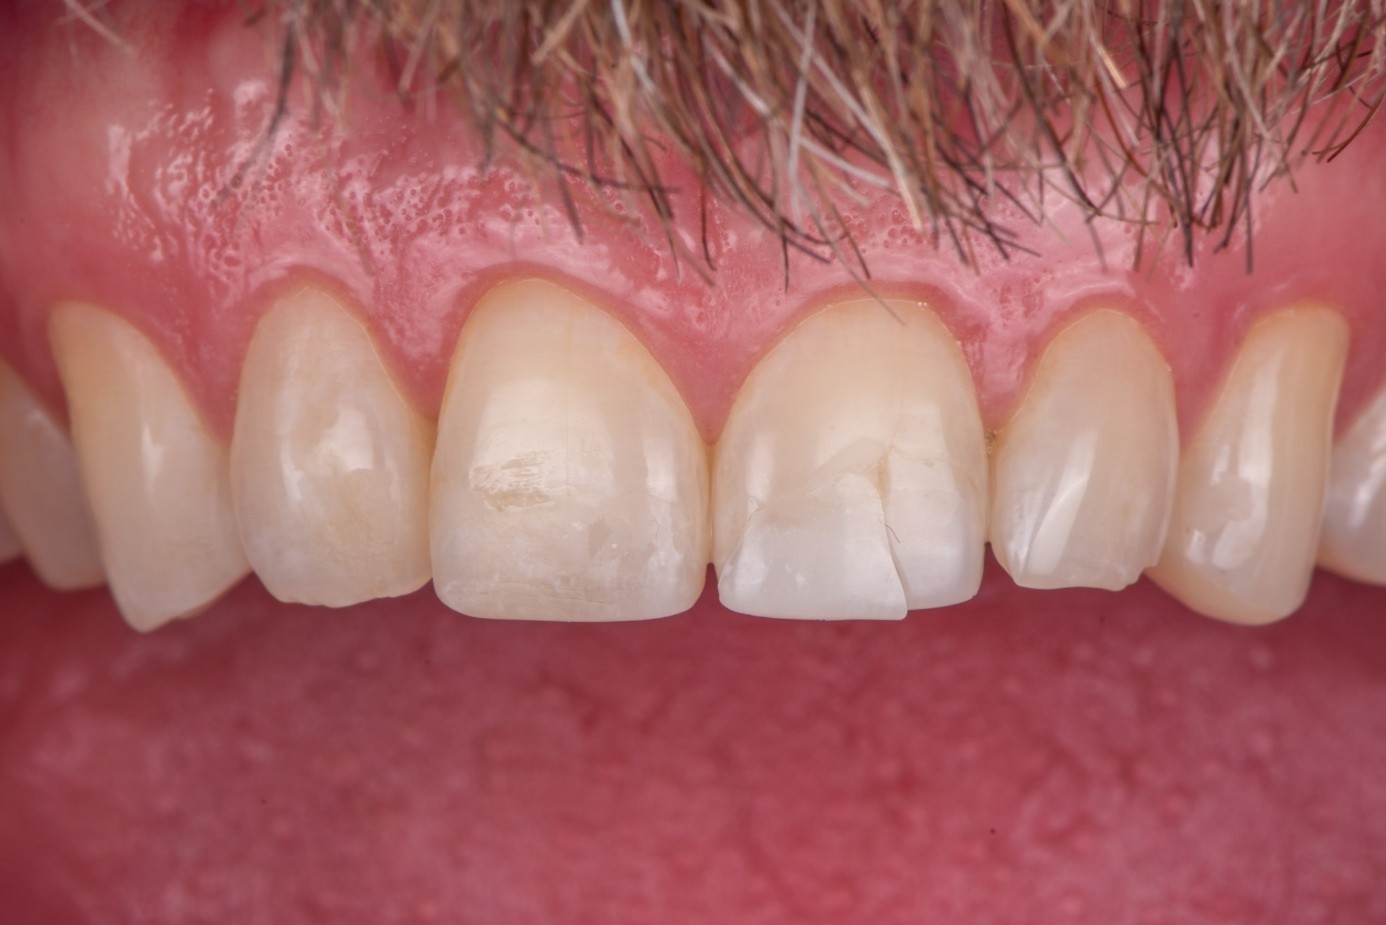

Case 2: Composite Facing Fracture

This case involved a patient with generalized mild anterior wear and an existing composite restoration on the maxillary left central incisor. The restoration extended from the middle third to the incisal edge and had excellent shade match and no marginal discoloration. The patient presented with a fractured central mesial portion of the composite (Figure 14 through Figure 16). Examination revealed a mixed failure pattern: Some adhesive and composite remnants remained on the tooth surface, while the fractured piece showed no residue internally. This finding suggested that the weak point was at the interface between composite and adhesive layer, with a minor cohesive component within the composite itself (Figure 17).

From a clinical standpoint, this pattern is reassuring, as it indicates a strong bond to the tooth substrate and that the restoration had functioned successfully until the composite material itself reached its fracture threshold. Considering the generalized wear pattern and patient history, parafunctional habits were suspected as the main cause of failure—the composite likely fractured when the applied functional stress exceeded its material strength.